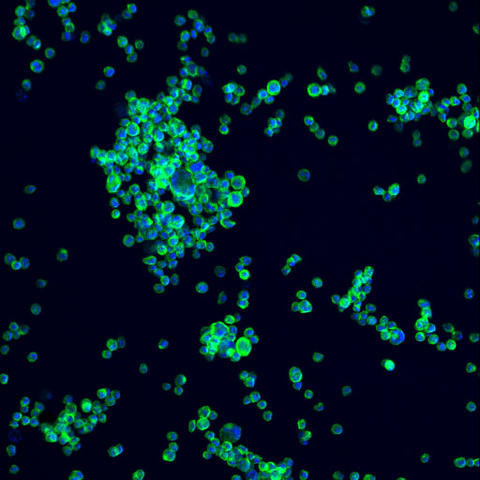

NIST, working with MilliporeSigma and NIIMBL, has released a living reference material called NISTCHO: clonal Chinese hamster ovary (CHO) cells engineered to produce the NIST monoclonal antibody (NISTmAb). Unlike the earlier single-use NISTmAb protein standard, NISTCHO is a renewable biological source (one millilitre contains ~10 million cells) that lets manufacturers, equipment makers and trainers see how cell culture, bioreactor design and downstream processing affect final antibody properties. The RM is formally released as Reference Material 8675 and includes measured controls such as gene-copy ratios to ensure vial-to-vial consistency.

- Each RM vial contains ~1 ml of suspension with approximately 10 million cells (Reference Material 8675).

Monoclonal antibodies (mAbs) are a major and growing class of therapeutics used across oncology, autoimmune disease and more. Historically, NIST provided a finished-protein standard (NISTmAb) to help labs check their measurement methods. However, because finished proteins cannot reveal how manufacturing steps affect product attributes, NIST and partners developed NISTCHO: a clonal CHO-K1 cell line that continuously produces the NISTmAb variant used in the original standard.

MilliporeSigma performed gene insertion and clone selection to isolate a high-producing, stable cell line. NIST characterised the cells and quantified metrics such as the gene-to-genome ratio so purchasers can rely on consistent behaviour within known uncertainty bounds. The living RM moves from research-grade material (first introduced in 2023) to a full reference material intended for reference measurements, quality assurance and method development.